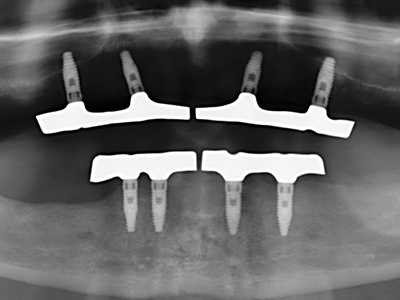

Bone tissue is not simply a mineral structure but also contains a substantial proportion of collagen fibres. This means it not only has good compressive strength but also a degree of flexibility, which can be taken advantage of when performing bone augmentations. In the classical expansion procedure using bone splitting, the atrophied alveolar ridge is split longitudinally and carefully expanded after reaching an adequate osteotomy depth (Fig. 13-16), ideally without substantial removal of the periosteum (Brugnami, Caiazzo et al. 2014, Stricker, Fleiner et al. 2014). Screw and plate systems with increasing expansion distance have proven effective in separating the two bone lamellae while remaining below the fracture threshold. In general, residual bone widths of at least 3–4 mm are required (Chiapasco, Zaniboni et al. 2006) to guarantee adequate flexibility and sufficient bone coverage of the future implants. If necessary, a vertical relief osteotomy on one or both sides can improve flexibility. A combination with additional augmentation techniques, particularly on the buccal side, has been described as an alternative to the classical technique.

The splitting procedure is particularly atraumatic and there is no significant loss of dimension when using piezosaws, and there are no significant differences between implants in split jaws and implants in an alveolar ridge without a bone deficit (Chiapasco, Zaniboni et al. 2006, Danza, Guidi et al. 2009). However, sufficient continuous irrigation is essential, particularly with locally restricted and deep splitting to prevent thermal stress in the apical osteotomy regions.